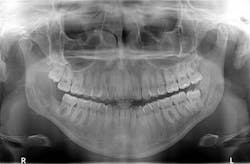

Figure 5: Radiograph taken immediately after surgery

The patient was referred to the oral surgeon for immediate surgery with enucleation (figure 5). A specimen was sent to the lab for pathology, and a liquid diet was recommended for six to eight weeks.